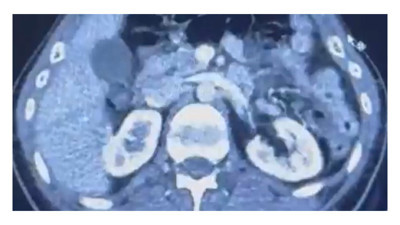

Kocaeli’de spor camiasının tanınan ve sevilen isimlerinden Hakan Aksoy beyninde oluşan bir tümör nedeniyle önce ameliyat sonrası yoğun bakıma alınmıştı. Yoğun bakıma kalbi duran Aksoy tüm müdahalelere rağmen kurtarılamayarak hayatını kaybetti